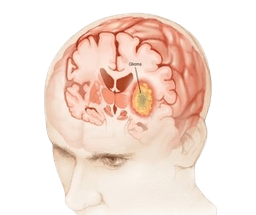

Gliomas

A glioma is a tumor that develops in the brain and spinal cord when the glial cells grow out of control. These cells support nerves and help the central nervous system. Gliomas usually grow in the brain and spinal cord. -br Gliomas are cancerous and grow slowly. They are primary brain tumors, these cells originate in the brain tissue. Gliomas don't usually spread outside of the brain or spine. These gliomas can be life threatening because they can: